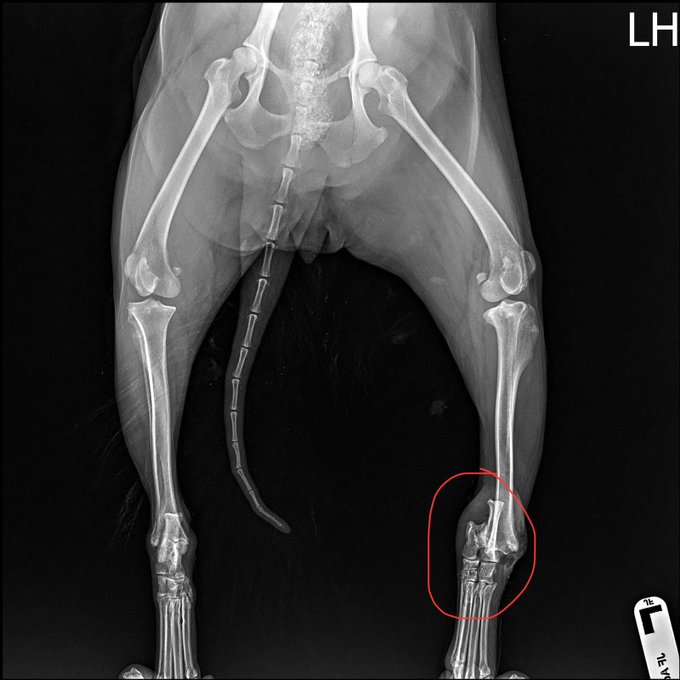

🦵 Sonradan ACL’sinin de yırtıldığını öğrendik.

İlk ameliyat başarısız oldu. Bacağı o kadar kötüydü ki plaka ve vida takılması gerekti. Ancak enfekte oldu ve başarısız oldu.

6 haftadır yürüyemediği için kasları zayıflamaya başladı. Durum pek iyi görünmüyordu. x.com